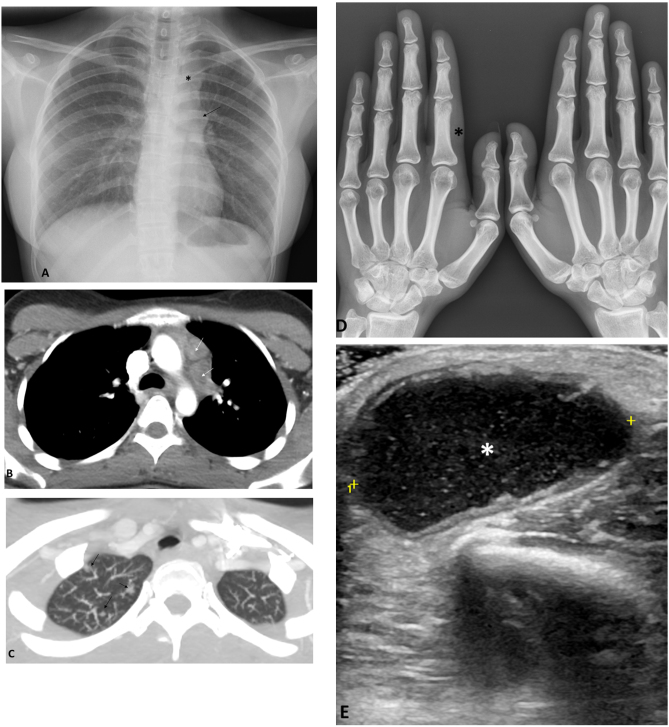

Figura 1.

A) Radiografía de tórax demuestra un moderado ensanchamiento mediastínico superior izquierdo (*), así como un hilio izquierdo prominente de morfología nodular (flecha). B) La TC torácica en la ventana de mediastino muestra adenopatías mediastínicas izquierdas, con centro hipodenso. C) En la TC torácica en la ventana de pulmón se observa algún nódulo subcentimétrico en el ápex derecho (flechas). D) En la radiografía de las manos se aprecia mínima tumefacción de partes blandas a nivel de la falange proximal del segundo dedo de la mano izquierda (*). E) La ecografía del codo derecho muestra la presencia de una colección (*), hipoecogénica y con ecos puntiformes en su interior, de 35 mm de diámetro máximo, ubicada en la partes blandas del codo derecho y compatible con absceso de partes blandas.